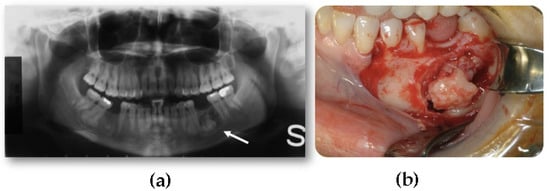

- Peripheral, consisting of periosteal development that can appear as a pedunculated mass (Figure 2);